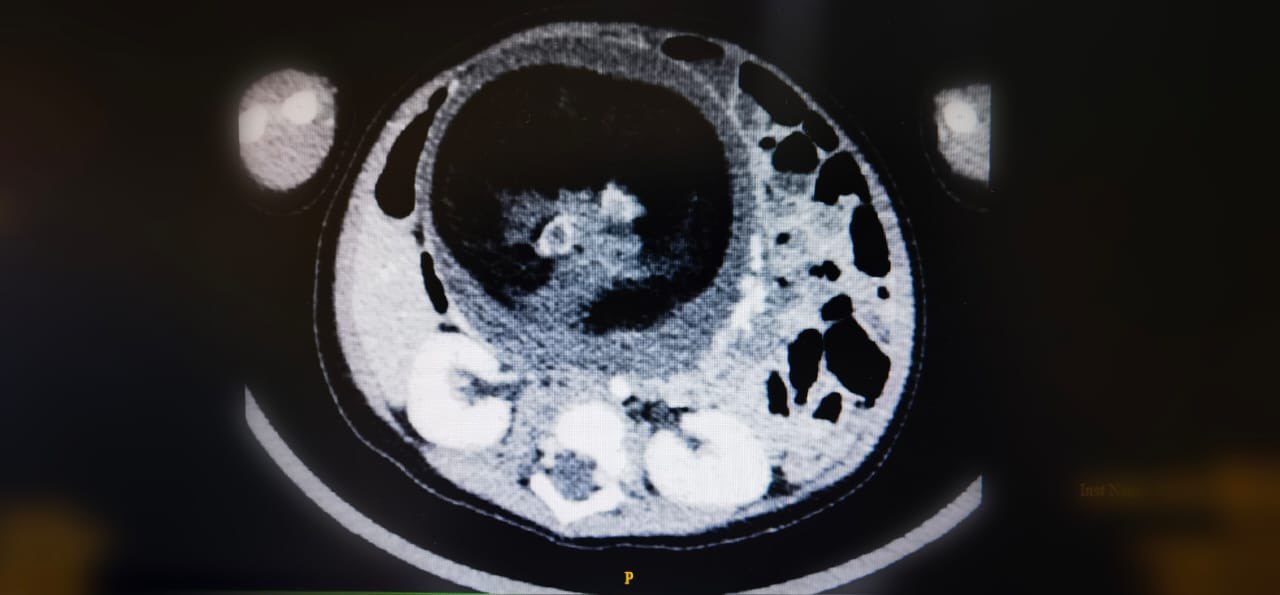

أجرى قسم جراحة الأطفال بالمستشفى السلطاني عملية جراحية نادرة تتمثل في استئصال جنين من داخل جنين، وهي حالة تعد نادرة الحدوث عالميا، لكونها تتم في ظروف استثنائية.

وأُجريت العملية لطفل يبلغ من العمر ثمانية أشهر،وبعد ثلاثة أيام من إجراء العملية تم التحقق من الفحوصات والمؤشرات التي أثبتت نجاح هذه العملية النوعية وسمح للطفل بمغادرة المستشفى.

يُذكر أن هذه الظاهرة الطبية تعرف ب” Fetus in feto” وتحدث بنسبة 1 من كل 500 ألف حالة ولادة حية على مستوى العالم.